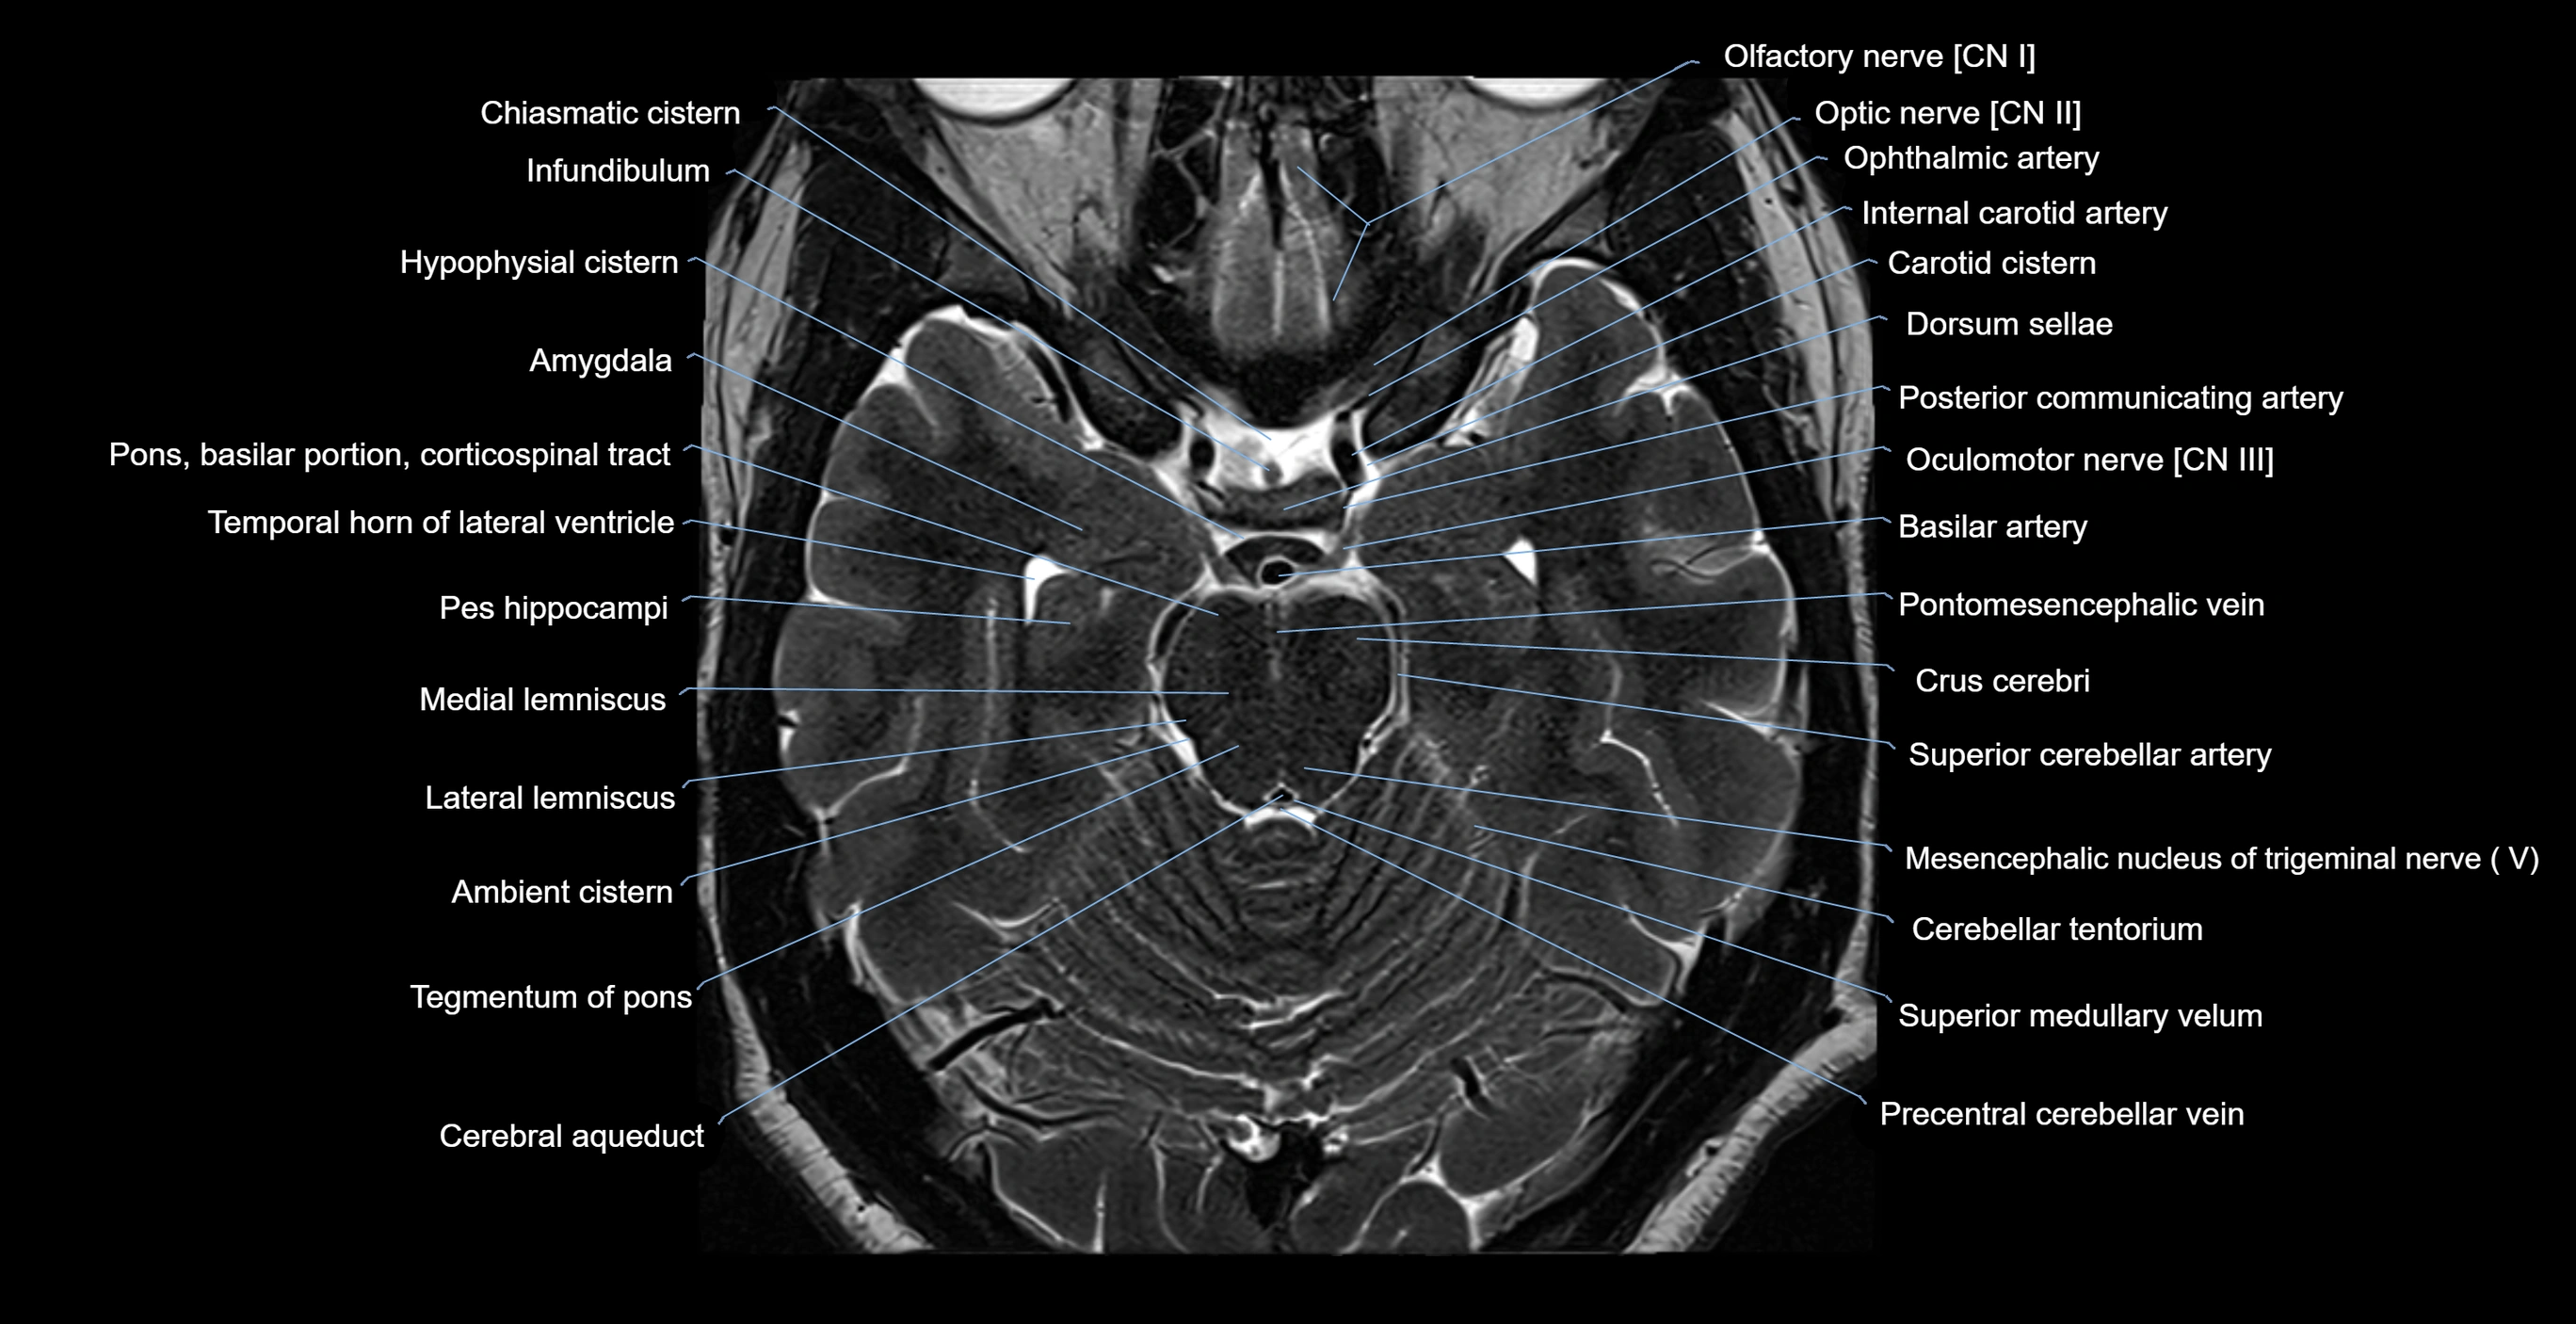

MRI images